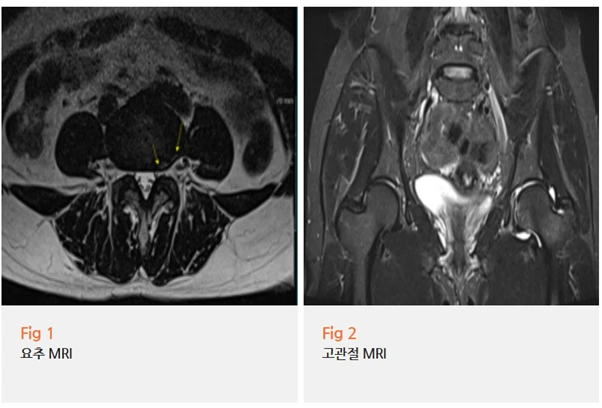

요추와 고관절을 모두 확인할 수 있는 MRI를 시행했습니다.

결과를 보는 순간,

환자분이 왜 이렇게 오래 고생하셨는지 알 수 있었어요.

✔️ 요추 4-5번 추간판 질환

✔️ 좌측 고관절 부위 염증 소견

✔️ 고관절충돌증후군

단순한 근육 긴장이 아니었던 거예요.

고관절 자체에 구조적인 문제가 있었고,

그로 인해 염증까지 생긴 상태였습니다.